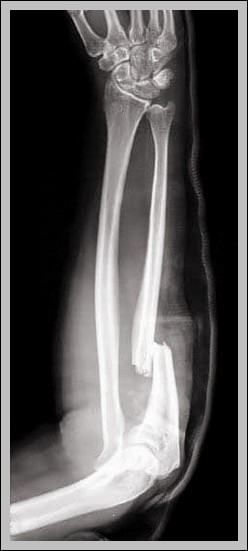

Monteggia fracture: proximal ulna fracture with radial head dislocation (anterior most common). Bado classification types I-IV; requires ORIF for ulna and radial head stability.

Monteggia Fracture of the Radius and Ulna Diagram